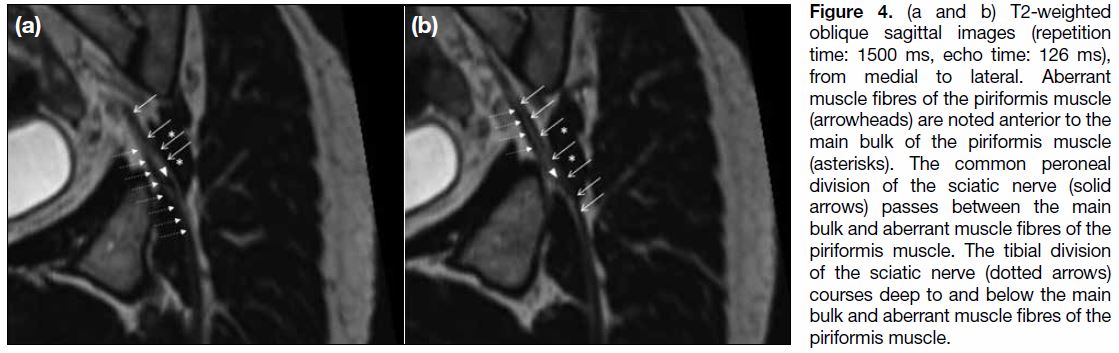

Figure 4. (a and b) T2-weighted

oblique sagittal images (repetition

time: 1500 ms, echo time: 126 ms),

from medial to lateral. Aberrant

muscle fibres of the piriformis muscle

(arrowheads) are noted anterior to the

main bulk of the piriformis muscle

(asterisks). The common peroneal

division of the sciatic nerve (solid

arrows) passes between the main

bulk and aberrant muscle fibres of the

piriformis muscle. The tibial division

of the sciatic nerve (dotted arrows)

courses deep to and below the main

piriformis muscle.